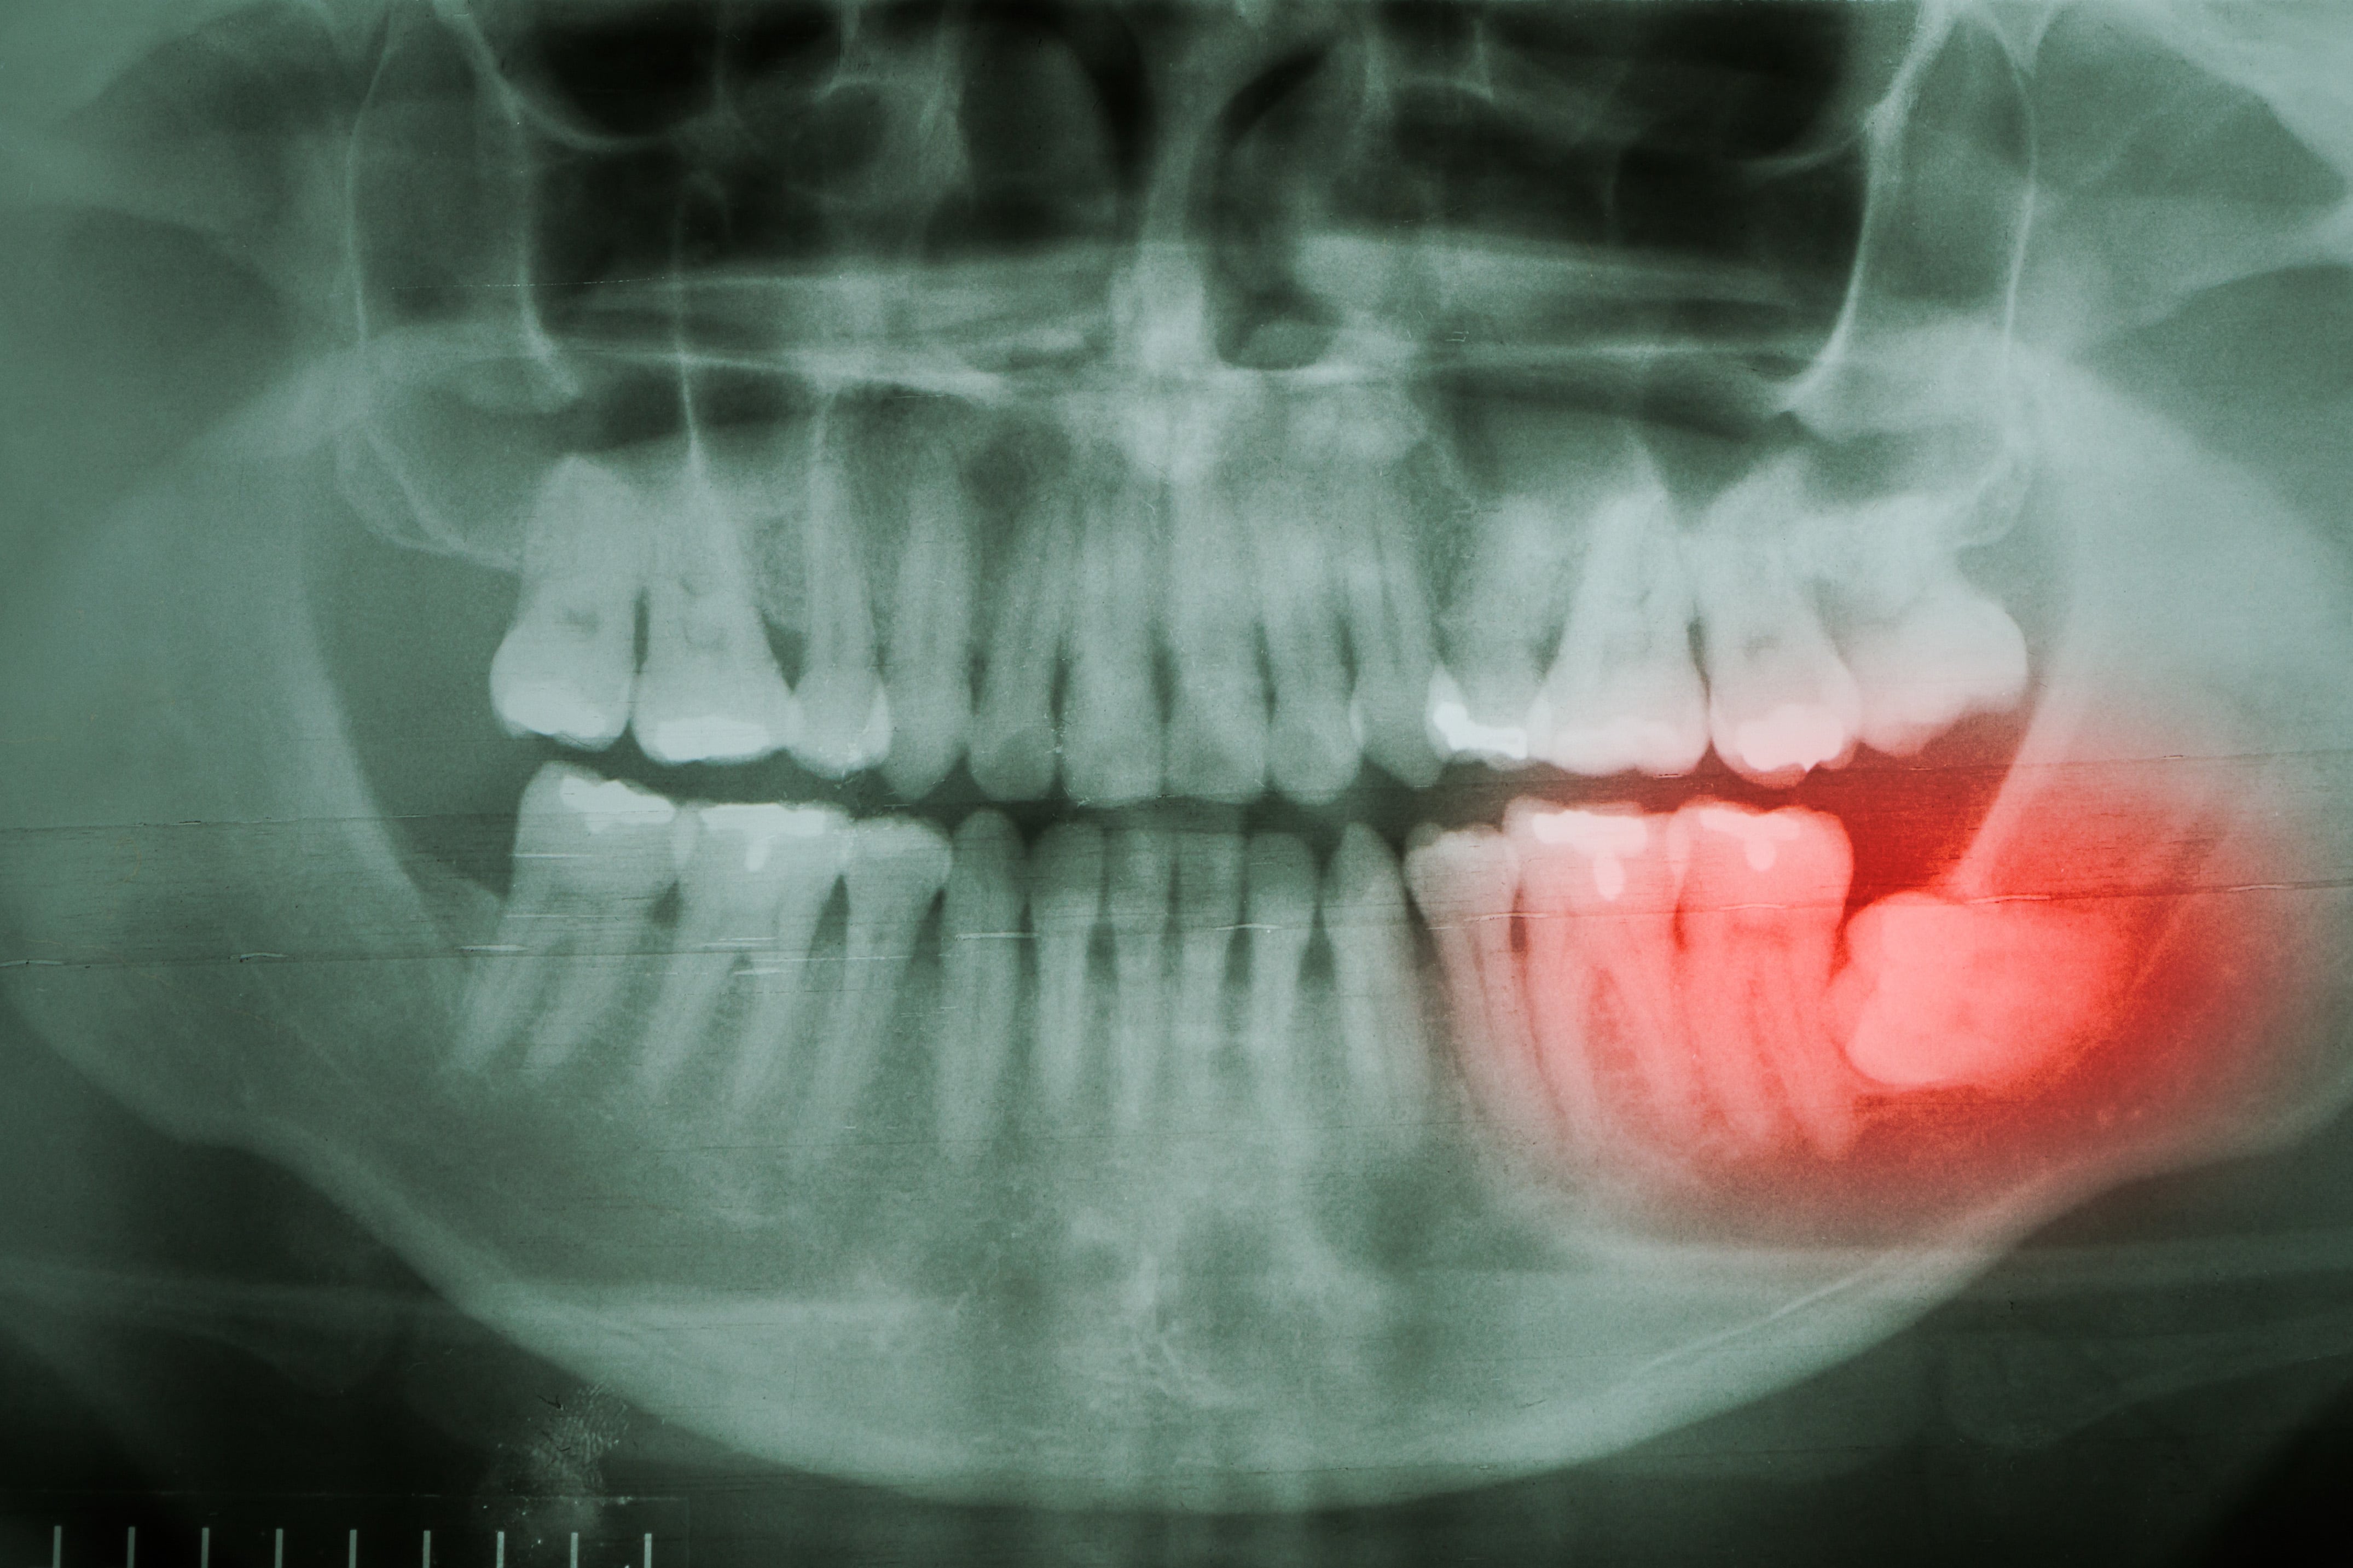

Abscessed Wisdom Tooth Xray

Abscessed Wisdom Tooth Xray is a high-quality image in the Rp collection, available at 1518 × 1136 pixels resolution — ideal for both digital and print use.

Understand why a wisdom teeth X-ray is essential for your oral health. Our guide explains how dental imaging detects impacted teeth, prevents jaw pain, and identifies potential infection risks. Learn what to expect during your diagnostic appointment and why professional X-ray analysis is crucial for planning safe, effective wisdom tooth extraction and long-term dental care.